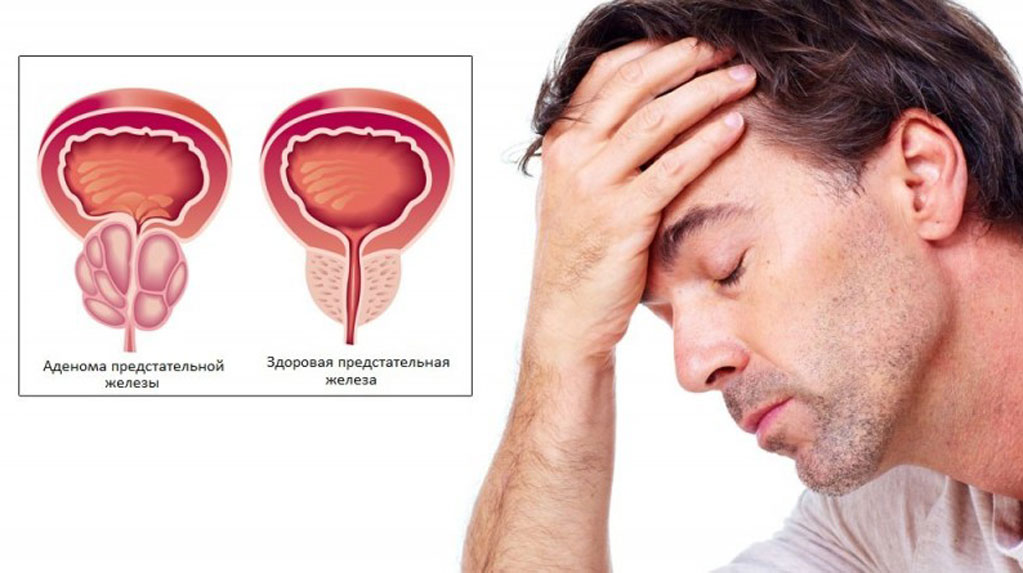

Prostat vəzinin quruluşu

Prostat vəzi –kiçik çanaqda, sidikliyin altında, sidik cinsiyyət diafraqmasının üzərində, qasıq bitişməsinin arxasında, düz bağırsağın önündə yerləşir və boz rəngdə olub sərt konsistensiyalıdır.

Prostat vəzinin çəkisi 20-25 q, köndələn ölçüsü 4 sm, boylama ölçüsü 3 sm, qalınlığı 2 sm qədərdir. Prostat vəzinin əsası sidikliyin yuxarı hissəsinə, zirvəsi isə sidik cinsiyyət diafraqmasına baxır. Prostat vəzinin ön və arxa səthləri vardır. Vəzin ön səthi qasıq bitişməsinə, arxa səthi düz bağırsaq ampuluna söykənir.

Prostat vəzinin adenoması nədir?

Prostat vəzinin adenoması — prostat vəzinin xoşxassəli şişidir. Buna görə də bu xəstəliyin digər rəsmi adı – prostat vəzinin xoşxassəli hiperplaziyası (boyüməsi). Prostat vəzinin adenoması kişilər arasında çox yayılmış xəstəlik olub, adətən, yaşı 40-dan yuxarı olan kişilərdə təsadüf edilir.